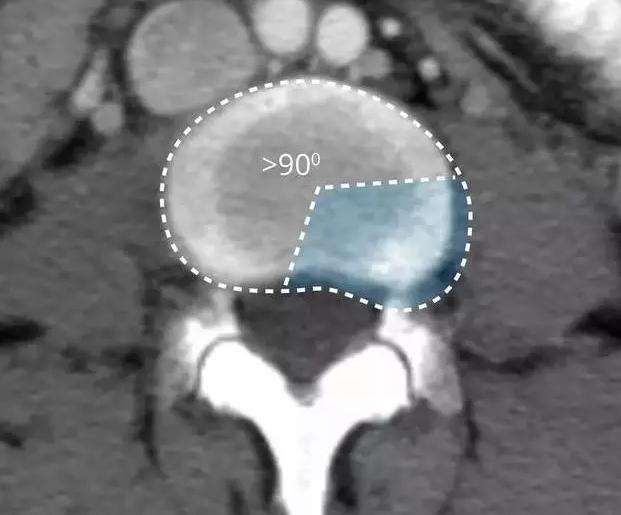

在影像学上表现为椎间盘局限性向椎管内突出。